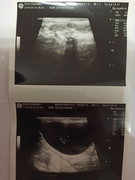

Сделали повторное узи 22.11. 2024 (первое было 09.11.2024). Высылаю фото и заключение.

Теперь ставят гидрометру и эндометрит. По мочевому мочекаменную.